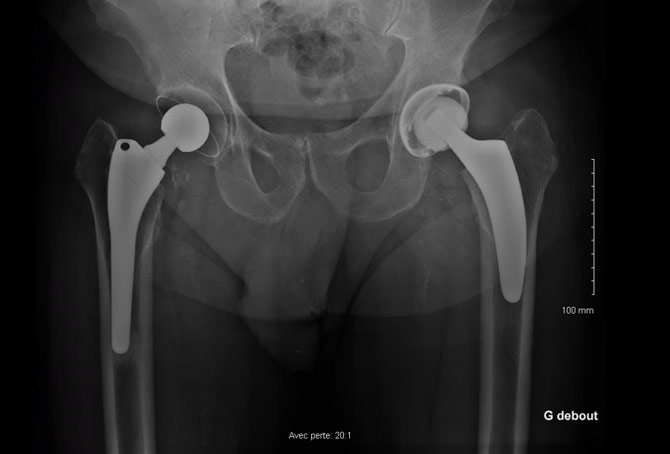

A 71-year-old male, who underwent a right Total Hip Arthroplasty (THA) 12 years ago and a left THA 5 years ago for hip osteoarthritis, recently experienced a fall while walking. Which classification system is appropriate for categorizing the fracture observed in the imagery, and what specific grade? Considering the patient's age, history of bilateral THA, and the nature of the fracture, how would you approach the management of this condition?

• 71 Y.O male

• Right THA 12 years ago and left THA 5 years ago for hip osteoarthritis

• Experienced a fall while walking

Previous X-rays

Which classification allows us to categorize this fracture and what is its grade?

• ✔️Vancouver classification grade B2